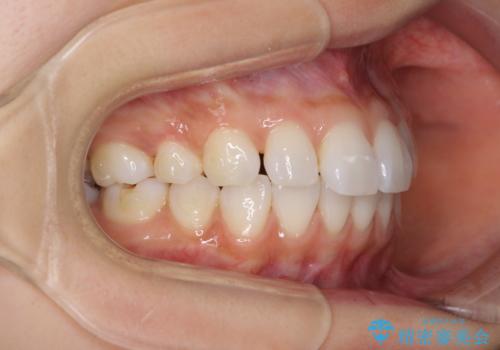

矯正治療の後戻り インビザラインによる再矯正治療

- 以前ワイヤー装置にて行った抜歯矯正の後戻りを気にして来院された患者様です。

前歯のデコボコにより、やや口元が突出した印象となっていたため、口元も引っ込めることとしました。

上下顎前歯に積極的にIPR(歯と歯の間を削る)を行い、インビザラインを用いて治療していくこととしました。

デコボコが解消されるのはもちろんのこと、突出感のあった前歯を引っ込めることができ、患者様には大変満足していただきました。